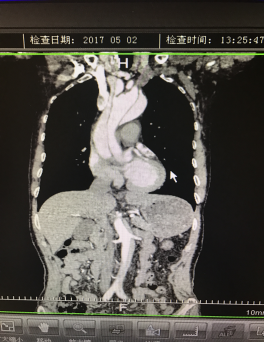

5月2號劉大伯照常早起干活,突然胸部劇烈疼痛,難以忍受,全身大汗,同時伴有右上肢發(fā)涼,他心想這次心絞痛比之前嚴重的多啊,趕緊叫上孩子到吉林國文醫(yī)院心血管內科住院,患者長期高血壓病史,血壓一直控制不理想,大夫給他做了檢查,測左上肢血壓:82/45mmHg,右上肢血壓測不出,心率52次/分,右側肱動脈、尺動脈、橈動脈搏動消失,左側股動脈搏動較右側弱。“糟了,雙側血壓差別這么大,是不是主動脈夾層了?”,接診大夫趕緊找來李主任,李主任反復詢問患者病情,表情突然凝重起來,患者胸痛這么明顯,血壓低的厲害,主動脈夾層的可能性很大。二話不說,李主任立即聯系影像科的醫(yī)生準備做主動脈CTA,移動患者做檢查的過程大夫們非常小心,嚴密監(jiān)測患者血壓變化情況。兩個小時后結果出來了,主動脈夾層從升主動脈一直撕裂到左側髂總動脈?。?!

從開始學醫(yī)到現在已經快9年了,主動脈夾層患者也見過一些,但像劉大伯這種危險類型的還是第一次見到,心里真的為他捏把汗,撕裂的主動脈隨時都有可能破裂,生命隨時可能終止,要知道主動脈夾層的死亡率非常的高,約50%的患者發(fā)病后48小時死亡,約90%的患者發(fā)病1個月內死亡。